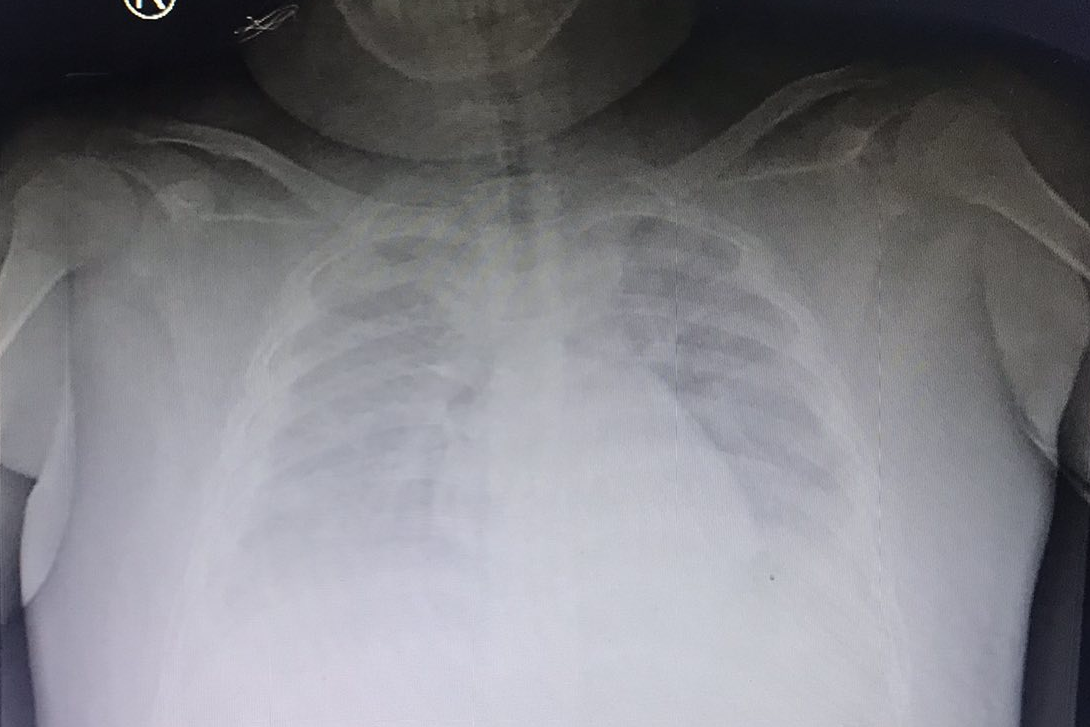

| Kết quả X-quang phổi ghi nhận, bệnh nhi tràn dịch màng phổi, tổn thương phổi 2 bên |

Các bác sĩ đã tiến hành xét nghiệm PCR và xác định, bệnh nhi còn dương tính với SARS-CoV-2. Trên siêu âm ổ bụng phát hiện tụ dịch dưới bao gan, phù nề túi mật, dịch tự do ổ bụng. Nghiêm trọng hơn, trẻ còn bị tràn dịch màng phổi 2 bên. Sau khi thực hiện thêm các xét nghiệm kiểm tra, các bác sĩ đã hội chẩn và chẩn đoán, bệnh nhi bị sốc sốt xuất huyết ngày 5 và mắc COVID-19 trên cơ địa béo phì.